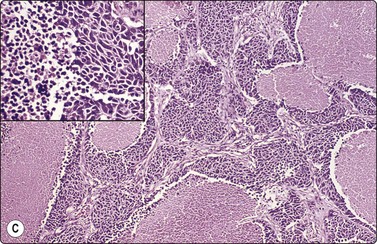

image image image

Fig. 8.35 Carcinoid tumor, spindle cell type

Tight aggregate of spindle cells with little pleomorphism. Cell block showing no mitotic activity or necrosis. Strong positive immunostaining for synaptophysin (A, H&E, HP; B, Cell block, H&E, HP; C, Cell block, IPOX, HP).

In ‘classic’ carcinoid tumors, the FNB findings are often distinctive enough to permit diagnosis, with or without ancillary tests such as immunocytochemistry. In contrast, the atypical carcinoids that we have seen were more difficult to classify before resection. Nicholson et al. found similar problems in recognizing a proportion of their neuroendocrine carcinomas, including low- and high-grade tumors, and suggested that ‘attention to the presence of loose cell aggregates in a background of singly dispersed cells; feathery patterns created by tumor cells clinging to capillaries; rosette formations; delicate, granular cytoplasm; inconspicuous nucleoli; molding in high-grade tumors; and, most importantly, speckled or dusty chromatin patterns are useful in identifying neuroendocrine differentiation in cytologic specimens’.36

Carcinoid tumors (Figs 8.33-8.35)32-36,238,246,247

Typical carcinoid33,35,36,246,247

Usual findings

Dispersed cell population with some trabeculae or palisades and small cell clusters,

A monomorphous population of small neoplastic cells with small amounts of intact cytoplasm,

Rounded or oval nuclei with stippled/granular nuclear chromatin and small nucleoli,

Plexiform background of small blood vessels; adherence of cells to vascular cores.